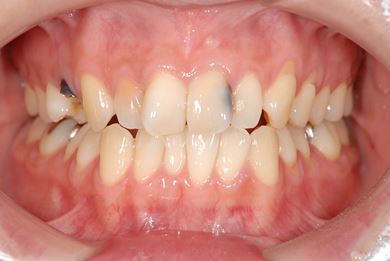

インプラント治療+セラミック治療

| カテゴリー | 【インプラント治療】【セラミック治療】 | ||||||||||||||||||||||||||||||||

| 性別/年齢 | 女性 / 30歳 | ||||||||||||||||||||||||||||||||

| 主訴 | 虫歯を治して欲しい。 | ||||||||||||||||||||||||||||||||

| 治療内容 | インプラント1本、メタルボンドセラミッククラウン1本、オールセラミッククラウン2本(オールセラミック用土台2本) | ||||||||||||||||||||||||||||||||

| 総治療費 | 703,238円 | ||||||||||||||||||||||||||||||||

| 治療期間 | 1年6ヶ月 |